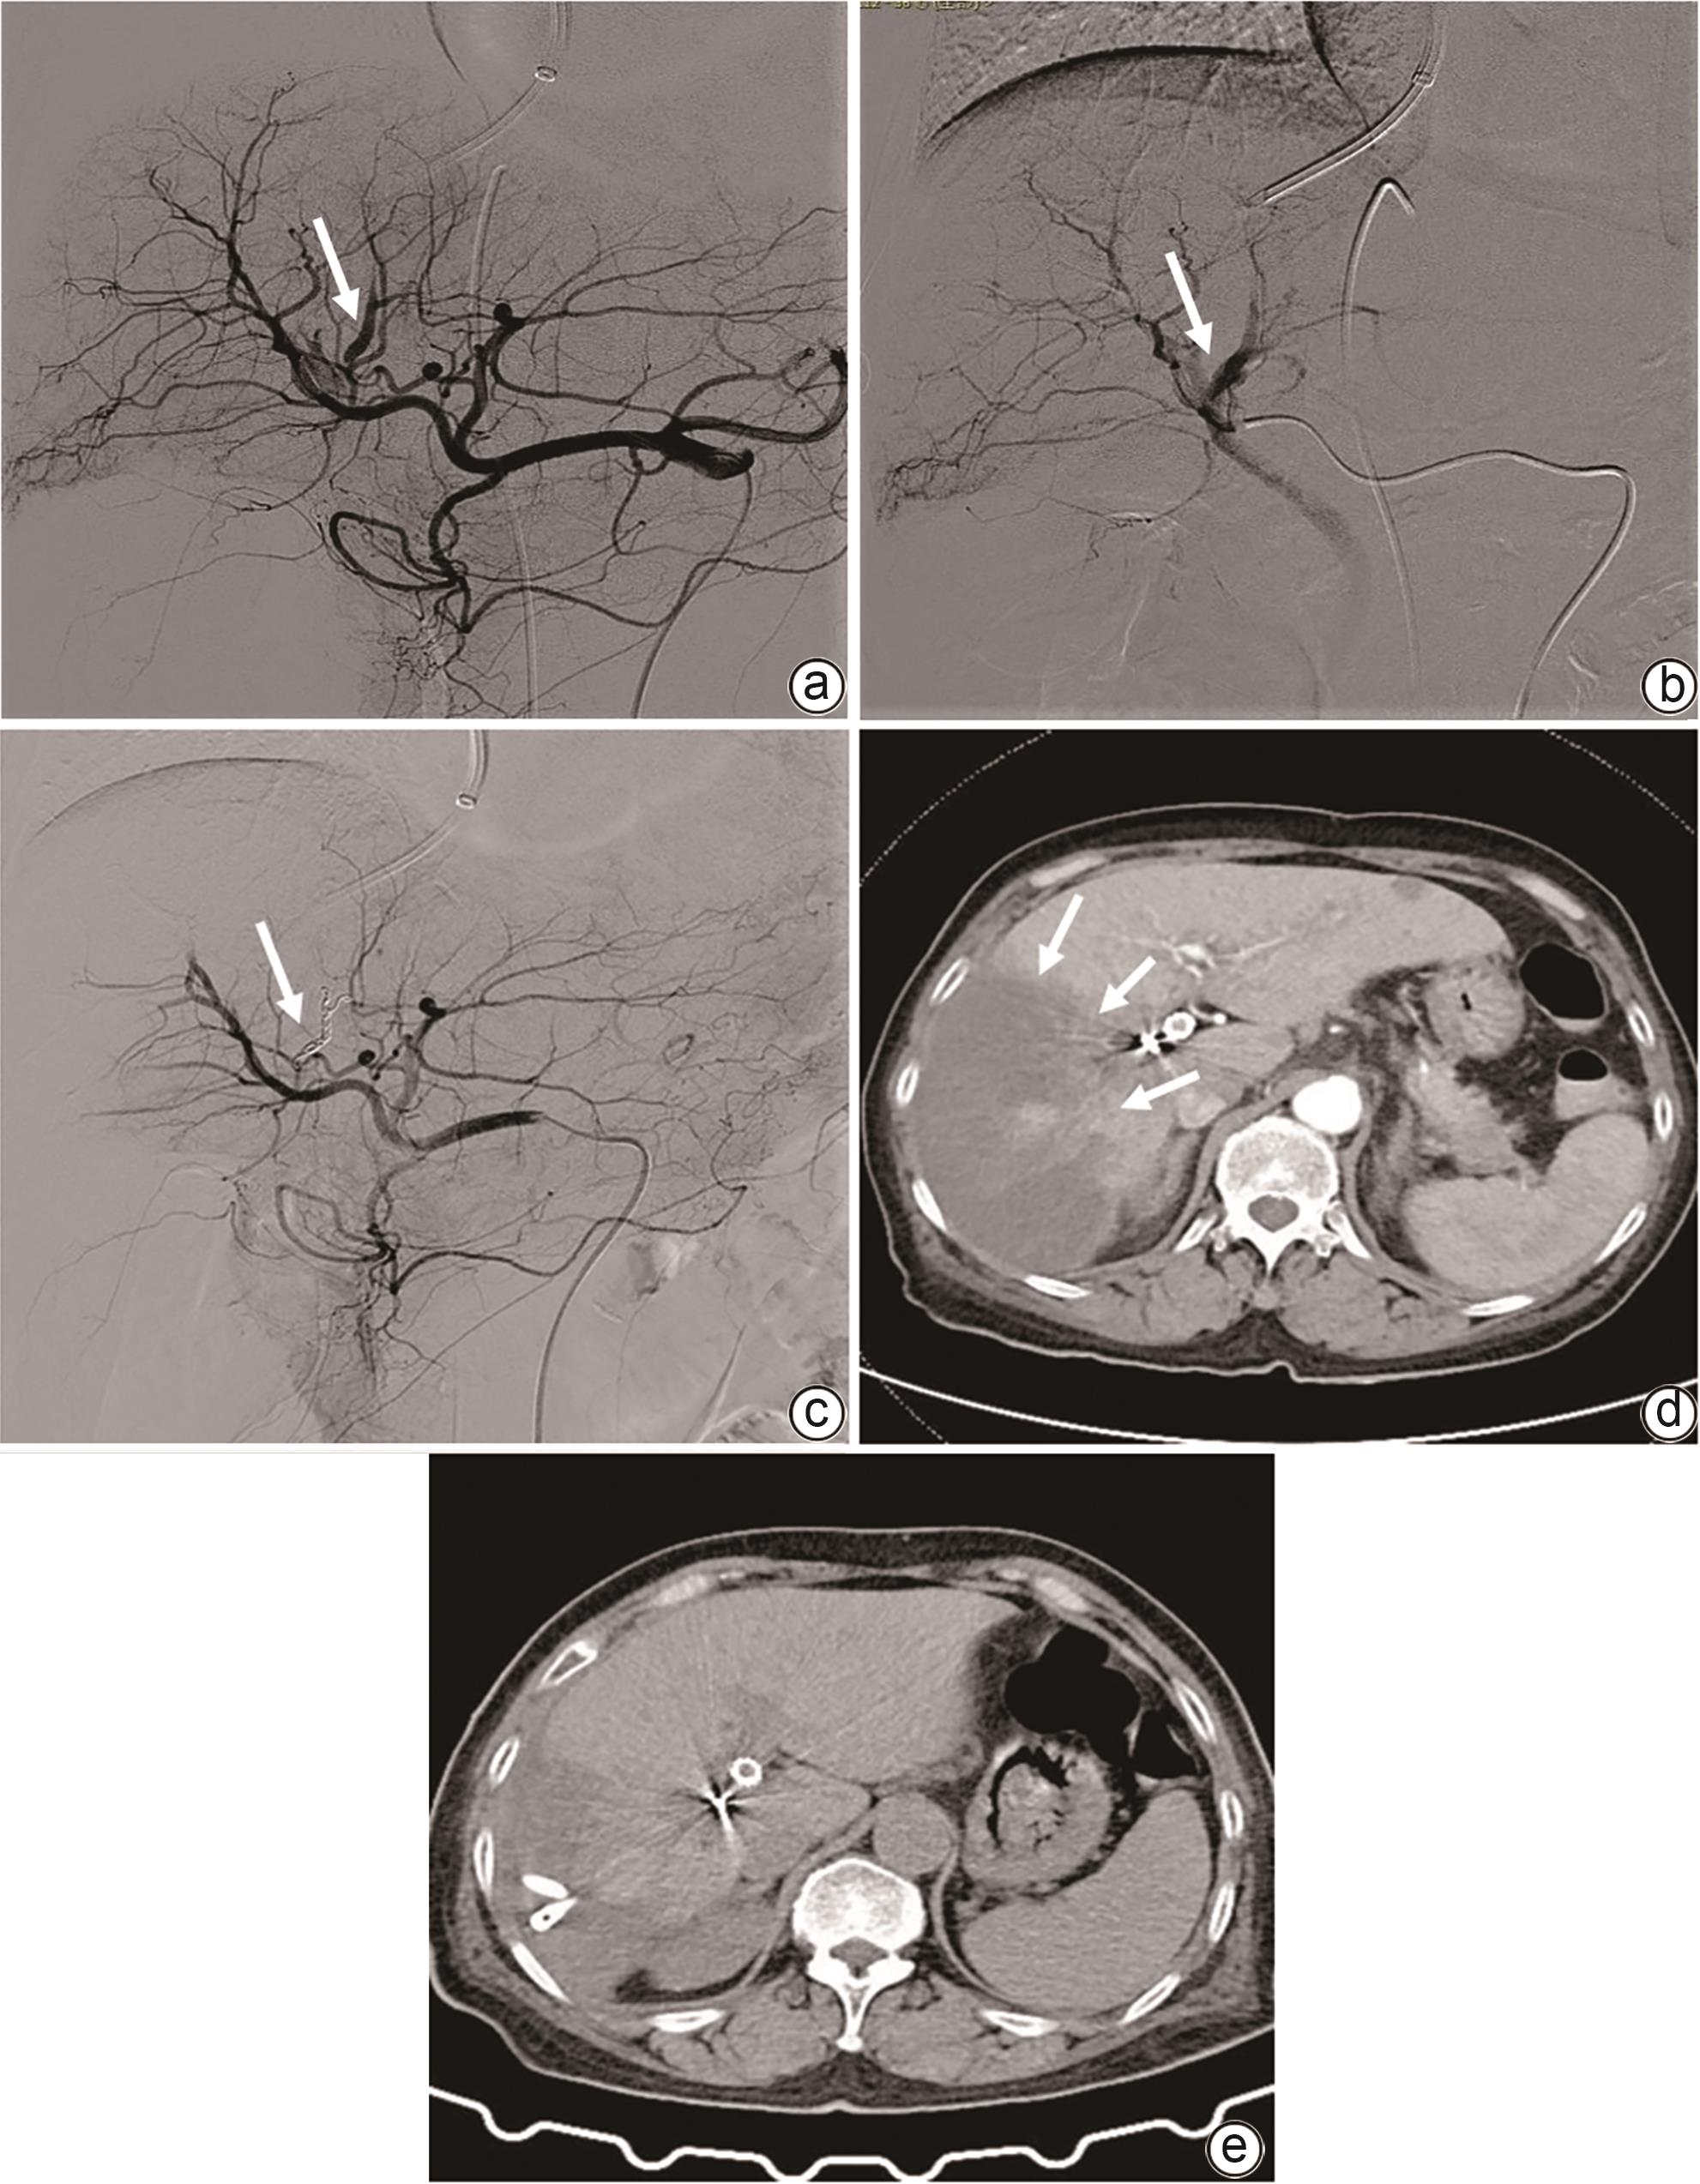

致命性医源性胆道出血的影像学特征和治疗对策

王晨, 王敏, 张科, 张金星, 刘莉, 范志宁

2024, 40(10): 2070-2074. DOI: 10.12449/JCH241022

摘要(987) HTML (349) PDF (2026KB)(76)

摘要:

目的  分析致命性医源性胆道出血(LIH)的影像学特征和发病机制,评价经动脉腔内治疗LIH的价值。  方法  收集2009年8月—2023年7月南京医科大学第一附属医院收治的上消化道出血住院患者269例,对其中确诊为LIH并得到治疗的24例患者的临床资料进行回顾性分析,包括LIH的医源性原因、血管造影结果和动脉腔内治疗方法。23例患者使用明胶海绵颗粒和弹簧圈进行动脉栓塞(TAE),1例患者使用覆膜支架进行隔离。评估疗效的主要标准是手术技术成功率、相关并发症和长期疗效的临床随访。  结果  12例LIH是由介入手术引起,12例是由肝胆胰外科手术所致。主要表现为显著的血压或持续血红蛋白下降(n=13)和上消化道出血(n=18)。2例患者在手术期间即出现症状,4例患者在24 h内出现症状,18例患者在24 h后出现症状。血管造影术显示出血阳性率为100%(24/24)。表现为假性动脉瘤(n=15)、肝动脉截断(n=3)、造影剂外渗(n=5)、肝动脉胆道瘘(n=3)。23例患者行TAE,1例患者行支架置入术。23例患者成功止血,技术成功率为95.8%(23/24)。4例TAE术后出现肝坏死和脓肿。治疗止血后无再出血复发。  结论  多种肝内外医源性损伤均可引起致命性胆道出血且临床及影像学表现多样。综合影像诊断联合动脉腔内治疗是LIH最佳的有效救命措施。